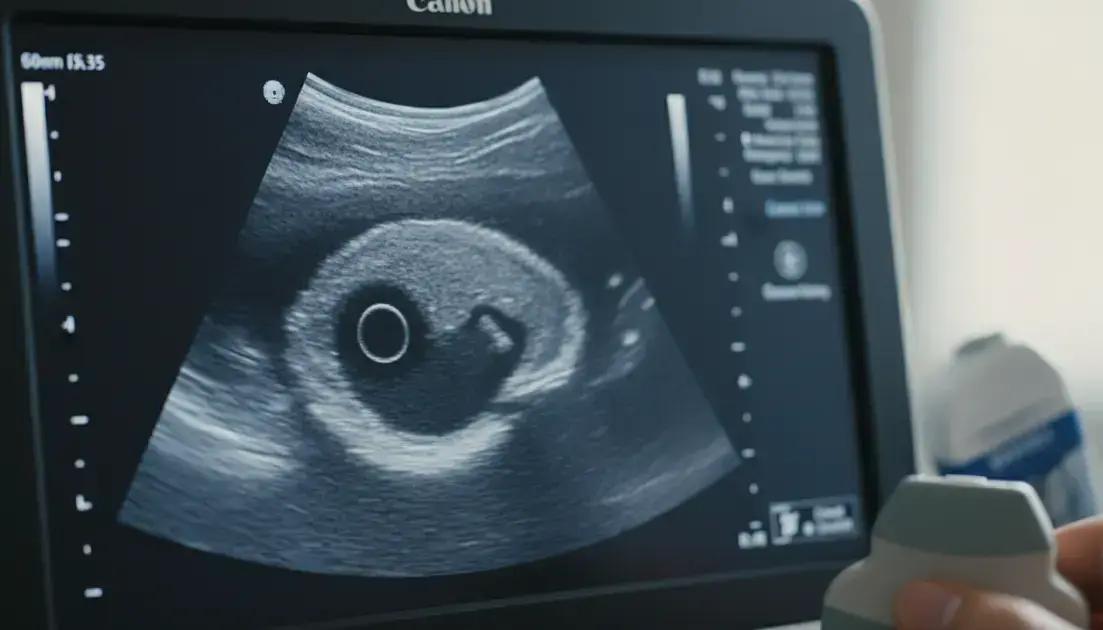

Um cisto anecoico é uma espécie de bolsa cheia de líquido que aparece dentro do nosso corpo. A palavra “anecoico” vem do grego e significa “sem eco”. Isso quer dizer que, quando os médicos fazem um ultrassom, essa bolsa não reflete as ondas sonoras. Por isso, ela aparece como uma área escura ou preta na imagem do exame. É como um balão de água dentro de você, que não tem nada sólido para as ondas baterem e voltarem.

A forma mais comum de descobrir um cisto anecoico é através de exames de imagem. O ultrassom é o principal deles. Durante o ultrassom, o médico desliza um aparelho sobre a pele. Esse aparelho envia ondas sonoras que viajam pelo corpo. Quando essas ondas encontram um cisto cheio de líquido, elas passam direto, sem criar ecos. É por isso que o cisto aparece escuro na tela. Outros exames, como a tomografia computadorizada ou a ressonância magnética, também podem identificar esses cistos.